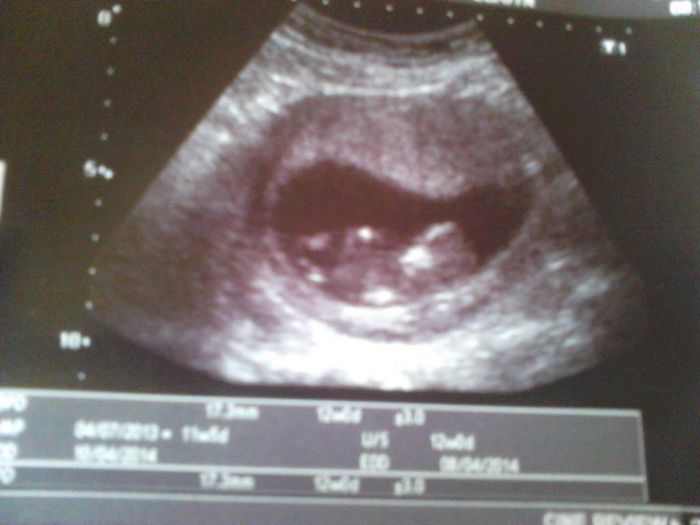

Mám tady fotku z minulého úterý, vypadá jako medvídek, ale fakt dokonelej

. Dneska bych měla být 13+0 a na další utz jdu až 22.10. Zaráží mě, že doktorka o žádným screeningu nemluvila. Jak to bylo u vás? Ptaly jste se na to? Nebo vás tam poslali automaticky? A platí se za to něco? Jinak u nás taky vše v pořádku.